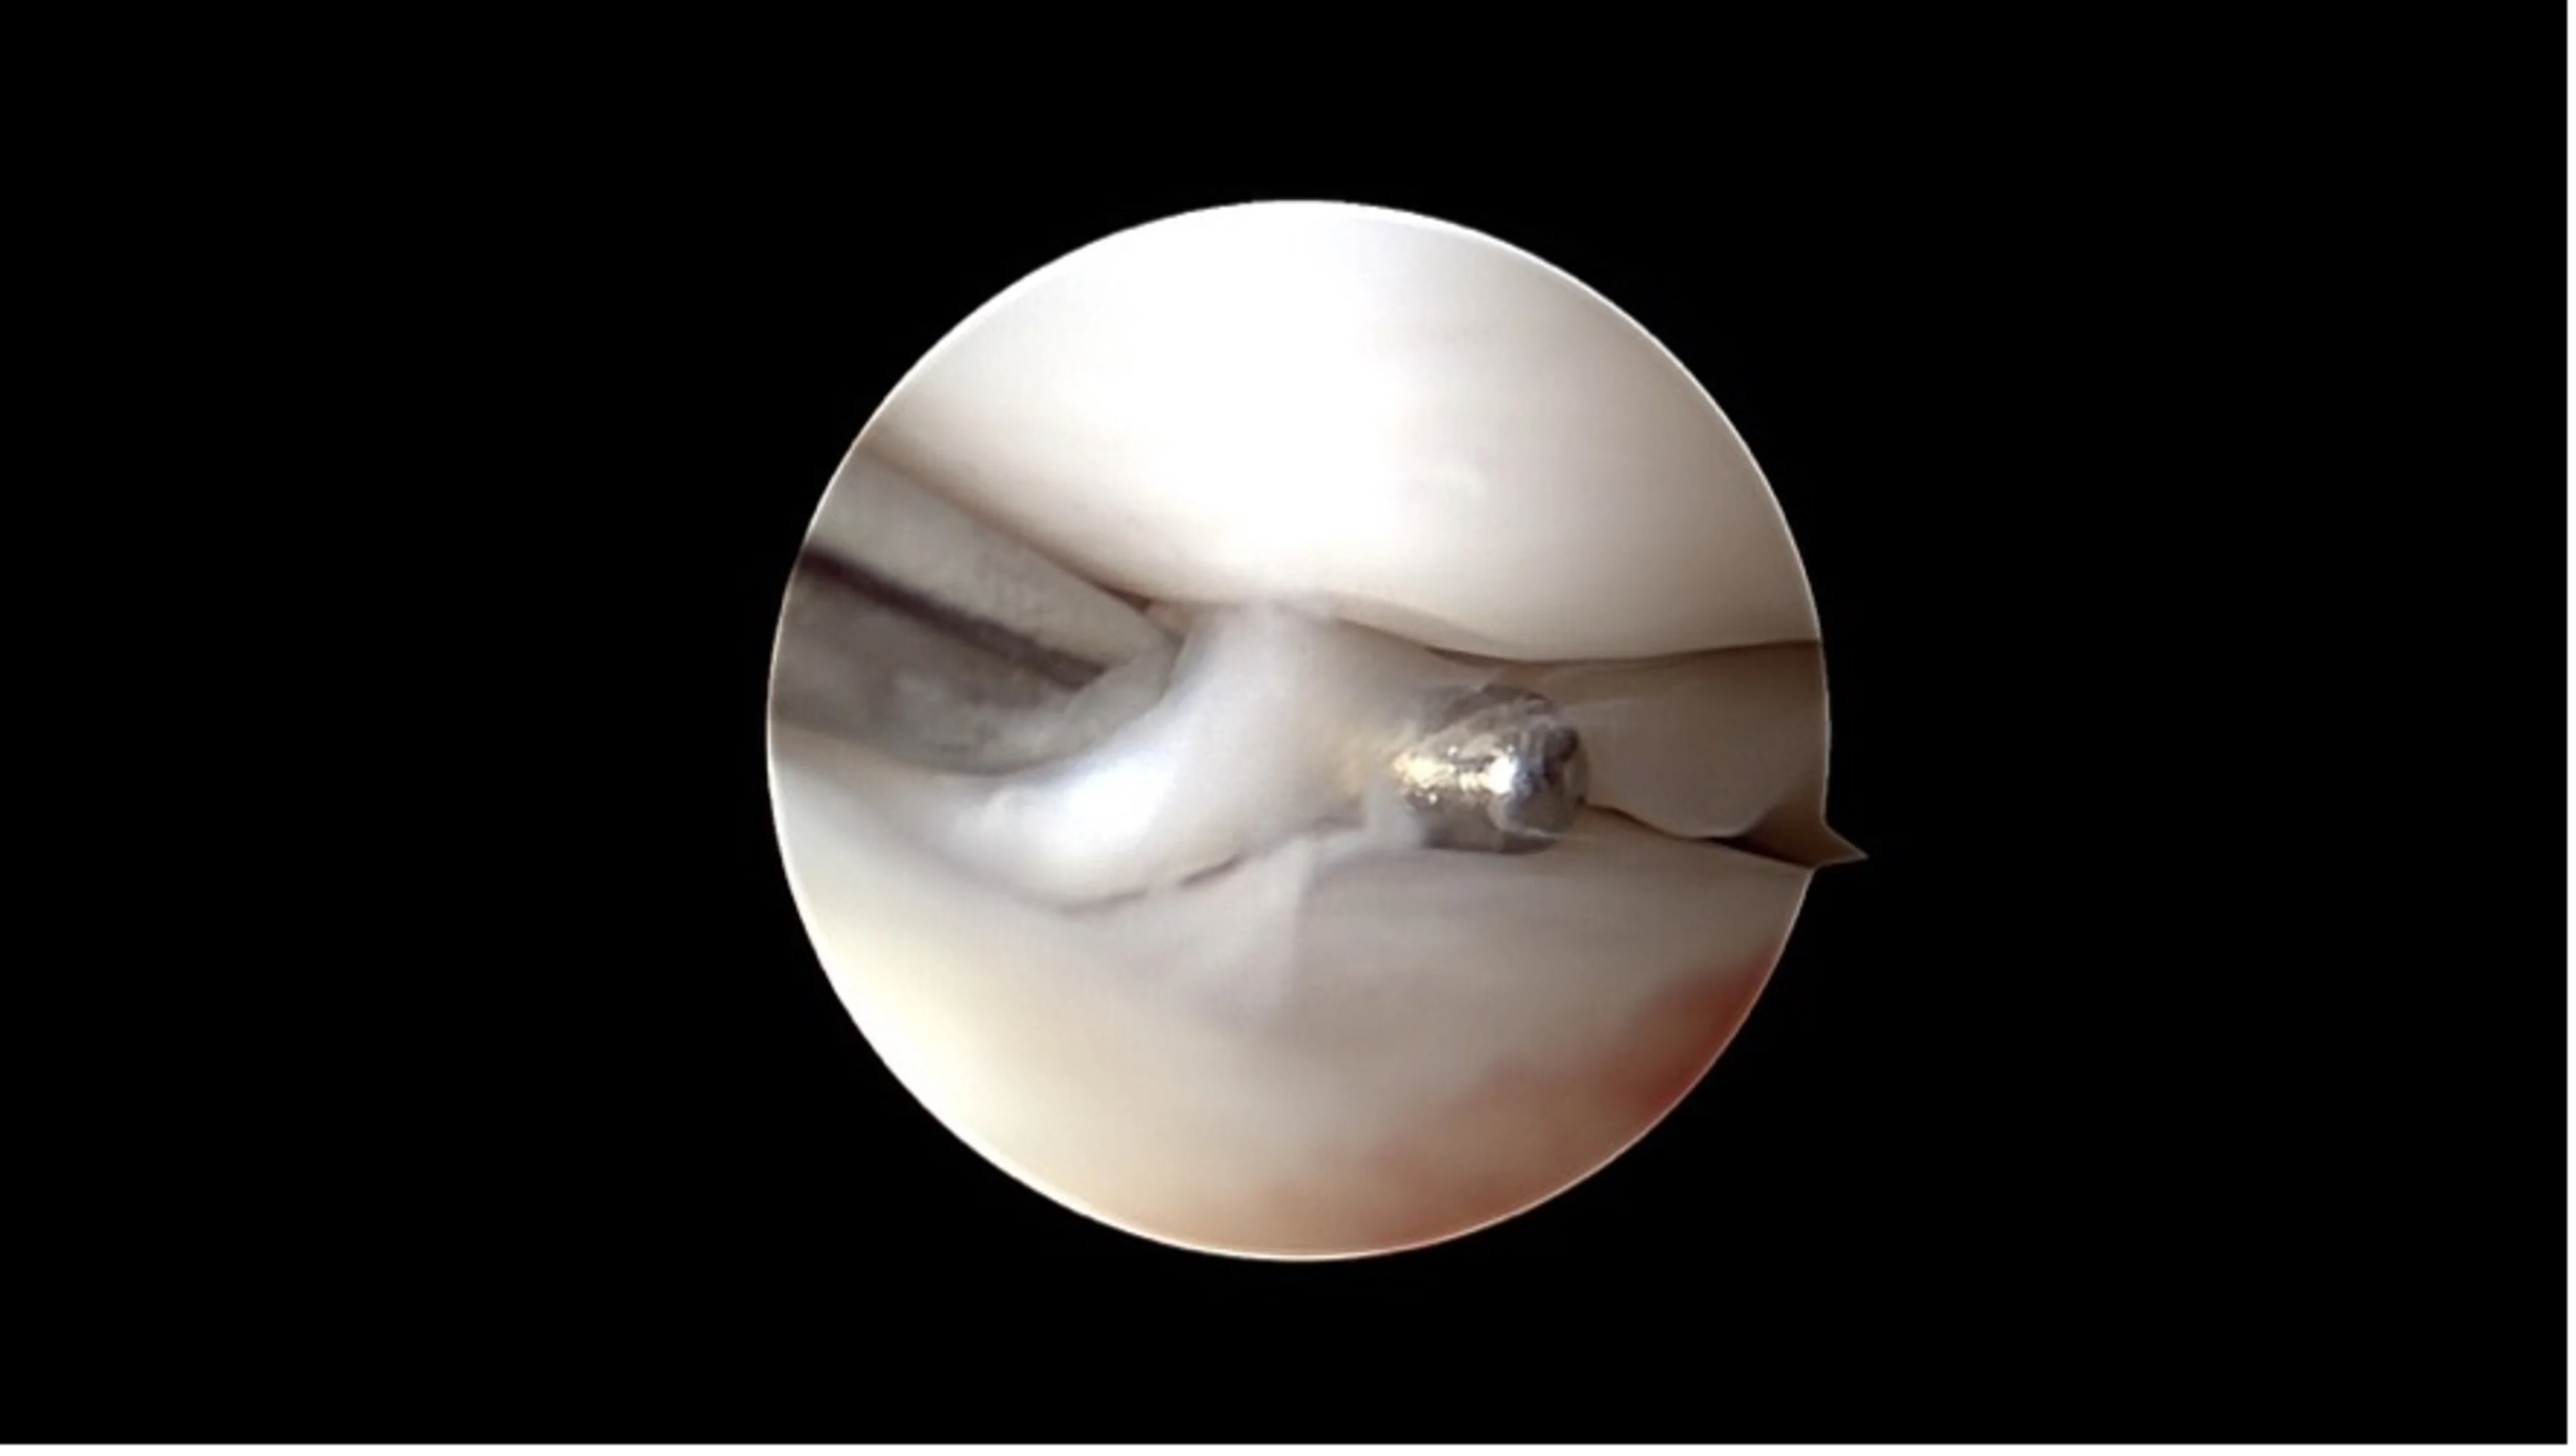

Rupture méniscale en anse de panier

Une caméra miniaturisée permet de visualiser directement l’intérieur de l’articulation par de petites incisions cutanées. Les lésions du ligament croisé et les dommages associés comme les déchirures du ménisque peuvent être diagnostiqués et souvent traités immédiatement.